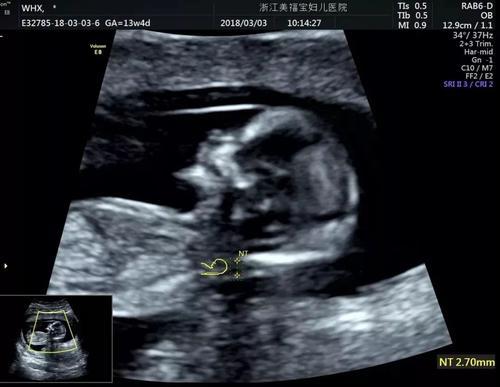

NT检查,是一个产检项目的简称,全称是:nuchal translucency,指的是“颈项透明层”,但并不是看孕妇的脖子,而是针对胎儿的检查,通过B超测算出肚子里胎儿的颈椎厚度(颈椎水平矢关切面皮肤至皮下软组织之间的最大厚度),它是整个孕期产检项目中重要的一项。

NT检查的临界值规定,在不同医院标准会有差异,的确有些医院是2.5mm为临界值,也有些是3.0mm或3.5mm。具体的以当地医院的诊断标准为诊断依据就好,如果以2.5mm为临界值,那只要测出来的厚度大于3mm就提示胎儿患唐氏症的风险较高,而且数值越大,风险越大。